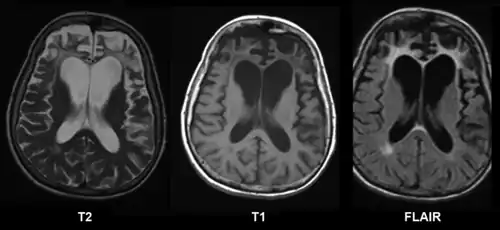

Brain CT with different grading systems of cerebral atrophy (seen as decreased size of gyri and secondary increased size of sulci):[19]

- Medial temporal lobe atrophy (MTA)

- Posterior atrophy (PA)

- Frontal cortical atrophy (fGCA)

CT and MRI are most commonly used to observe the brain for cerebral atrophy. A CT scan takes cross sectional images of the brain using X-rays, while an MRI uses a magnetic field. With both measures, multiple images can be compared to see if there is a loss in brain volume over time.[20]